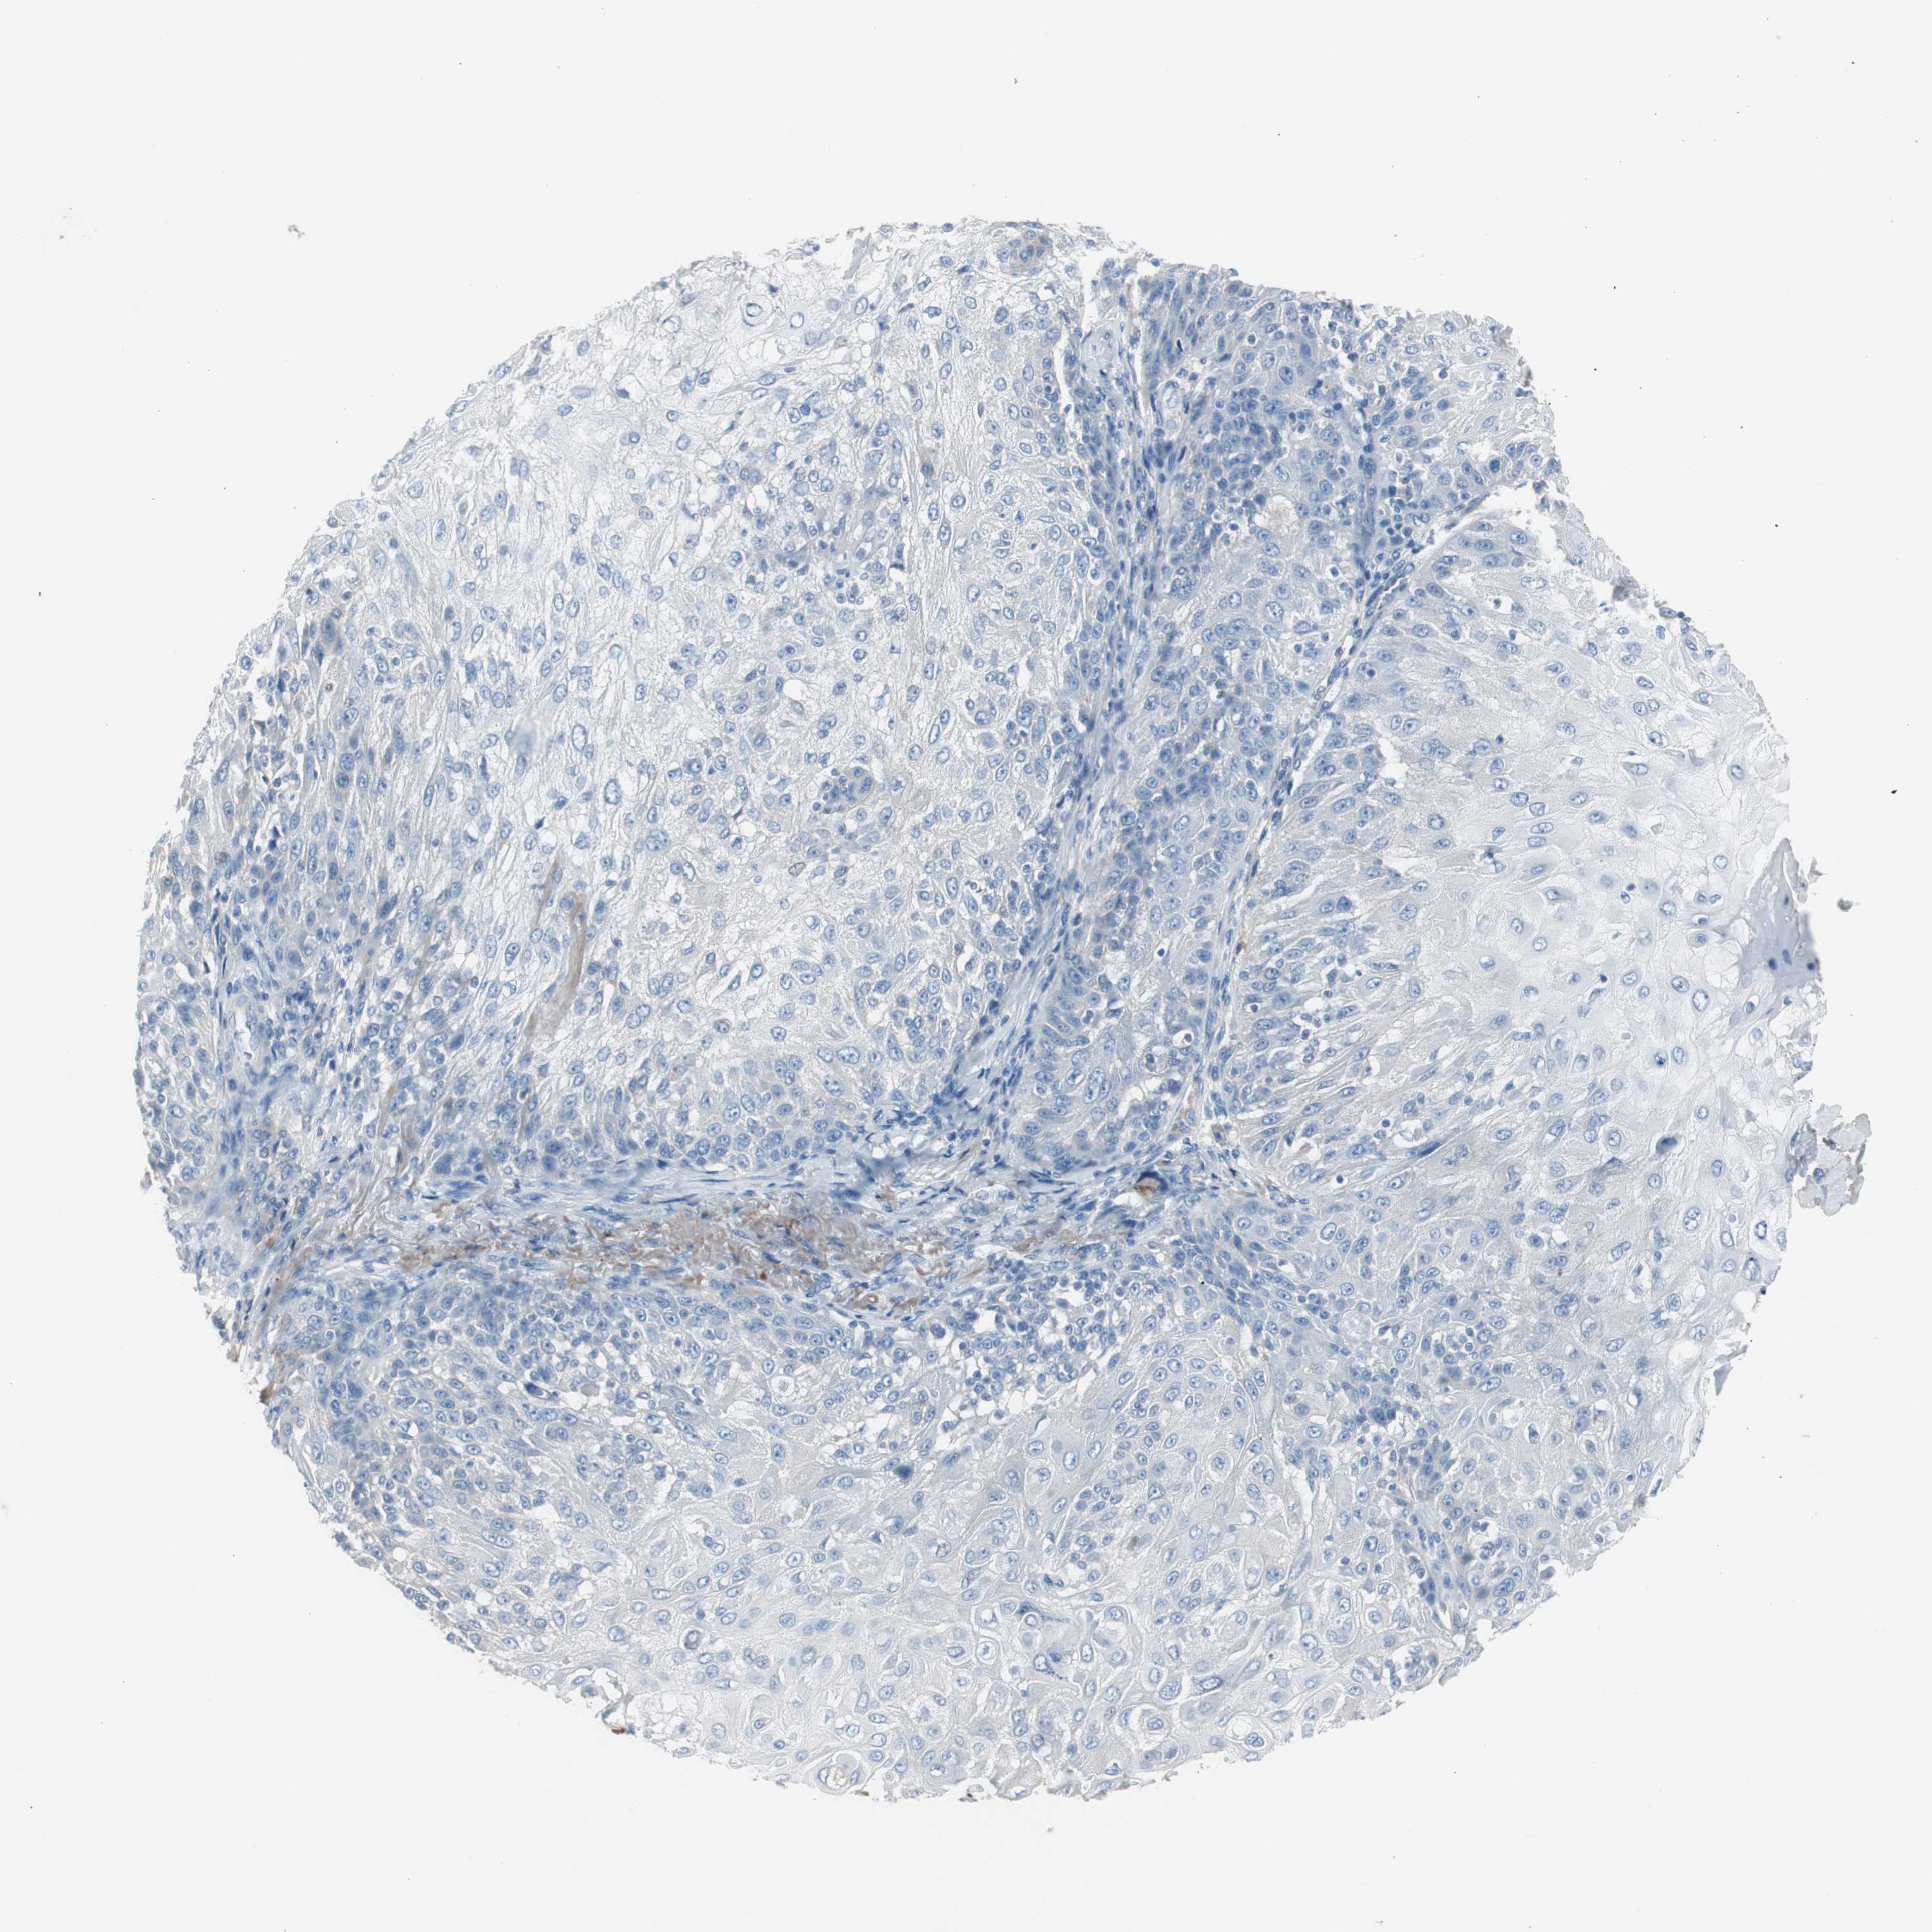

SKIN CANCER - Protein expressioni

A mouse-over function shows sample information and annotation data. Click on an image to view it in a full screen mode. Samples can be filtered based on level of antibody staining by selecting one or several of the following categories: high, medium, low and not detected. The assay and annotation is described here.

Antibody stainingi

Antibody staining in the annotated cell types in the current human tissue is reported as not detected, low, medium, or high, based on conventional immunohistochemistry profiling in selected tissues. This score is based on the combination of the staining intensity and fraction of stained cells.

Each image is clickable and will lead to virtual microscopy that enables deeper exploration of all samples and also displays staining intensity scores, fraction scores and subcellular localization as well as patient and tissue information for each sample.

Antibody HPA005825

Squamous cell carcinoma, NOS

Basal cell carcinoma